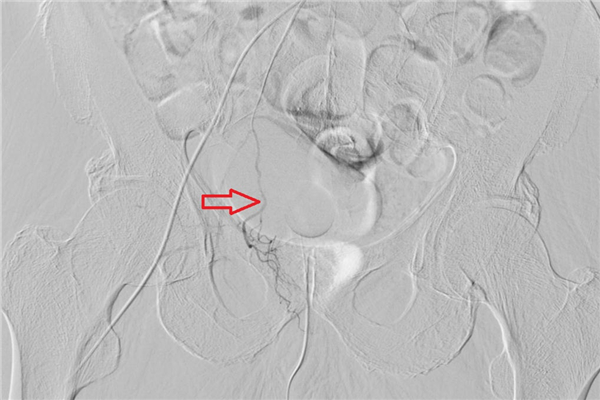

陈主任对老人的左侧前列腺动脉进行栓塞,阻断了对增生部位的供血,再次造影显示,前列腺动脉和前列腺染色均消失(如下图)。